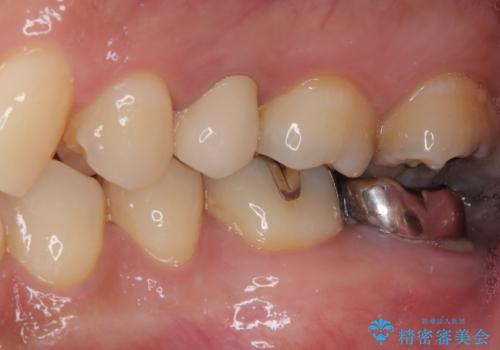

- 放置していたむし歯を治療したいとのことで来院された患者様です。

仕事が忙しいことを言い訳に虫歯を放置してきたものの、強い痛みを感じたことがあったため、重い腰を上げて来院されたとのことでした。

強い痛みのあった歯は、既に神経組織が失活しており根管治療が必要でした。

反対側の歯は、歯根だけが歯肉に埋もれて残っている状態のため、抜歯が必要な状態でした。

歯根だけとなっている歯はインプラントに、神経組織の失活している歯は根管治療を行い、いずれもオールセラミッククラウンにて補綴治療を行うこととしました。